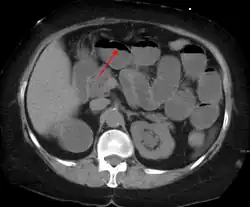

Causes of bowel obstruction include adhesions, hernias, volvulus, endometriosis, inflammatory bowel disease, appendicitis, tumors, diverticulitis, ischemic bowel, tuberculosis and intussusception.[1][2] Small bowel obstructions are most often due to adhesions and hernias while large bowel obstructions are most often due to tumors and volvulus.[1][2] The diagnosis may be made on plain X-rays; however, CT scan is more accurate.[1] Ultrasound or MRI may help in the diagnosis of children or pregnant women.[1]

The main diagnostic tools are blood tests, X-rays of the abdomen, CT scanning, and ultrasound. If a mass is identified, biopsy may determine the nature of the mass.

Radiological signs of bowel obstruction include bowel distension (small bowel loops dilated >3 cm) and the presence of multiple (more than 2) air-fluid levels on supine and erect abdominal radiographs.[16] Ultrasounds may be as useful as CT scanning to make the diagnosis.[17]

Contrast enema or small bowel series or CT scan can be used to define the level of obstruction, whether the obstruction is partial or complete, and to help define the cause of the obstruction. The appearance of water-soluble contrast in the cecum on an abdominal radiograph within 24 hours of it being given by mouth predicts resolution of an adhesive small bowel obstruction with sensitivity of 97% and specificity of 96%.[18]